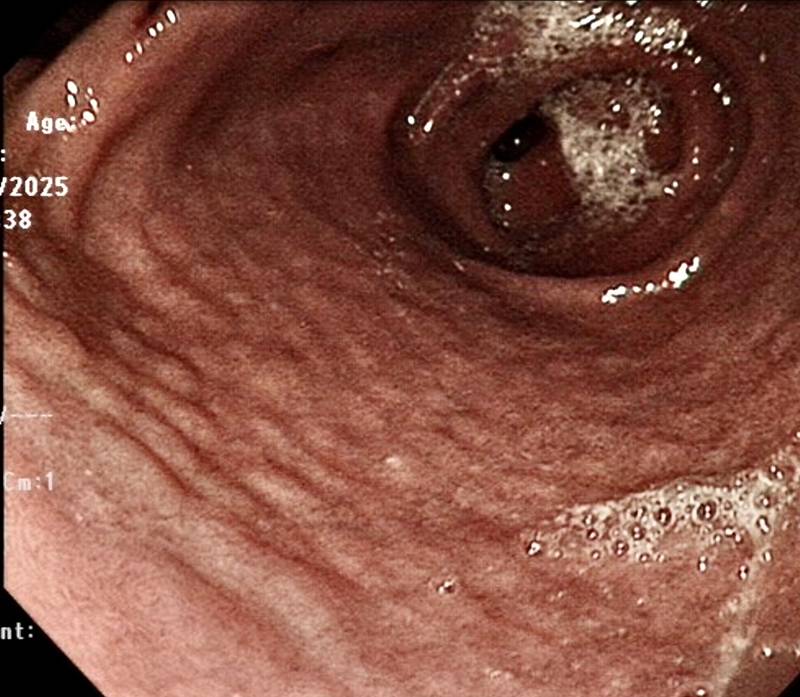

วันที่ 4 เมษายน 2569 เว็บไซต์ ETtoday รายงานเหตุอุทาหรณ์สำหรับครอบครัว ไม่ควรนิ่งนอนใจต่อการปวดท้องของลูก ๆ โดย ดร.หงฮวาซี กุมารแพทย์โรคระบบทางเดินอาหารและตับ จากไต้หวัน ได้ออกมาเล่าเคสของเด็กชายวัย 15 ปี ที่เข้ารับการรักษาในโรงพยาบาล หลังอาเจียนเป็นเลือดอย่างรุนแรง แถมยังส่องกล้องกระเพาะอาหารพบแผลที่มีเลือดออก รวมถึงพบการเปลี่ยนแปลงของเยื่อบุกระเพาะอาหาร จนมีลักษณะเป็นตุ่มเล็ก ๆ เรียงรายไปทั่ว ราวกับมีก้อนกรวดเล็ก ๆ กระจายตัว

ภาพจาก เฟซบุ๊ก 肚肚醫師-洪華希 兒童腸胃科